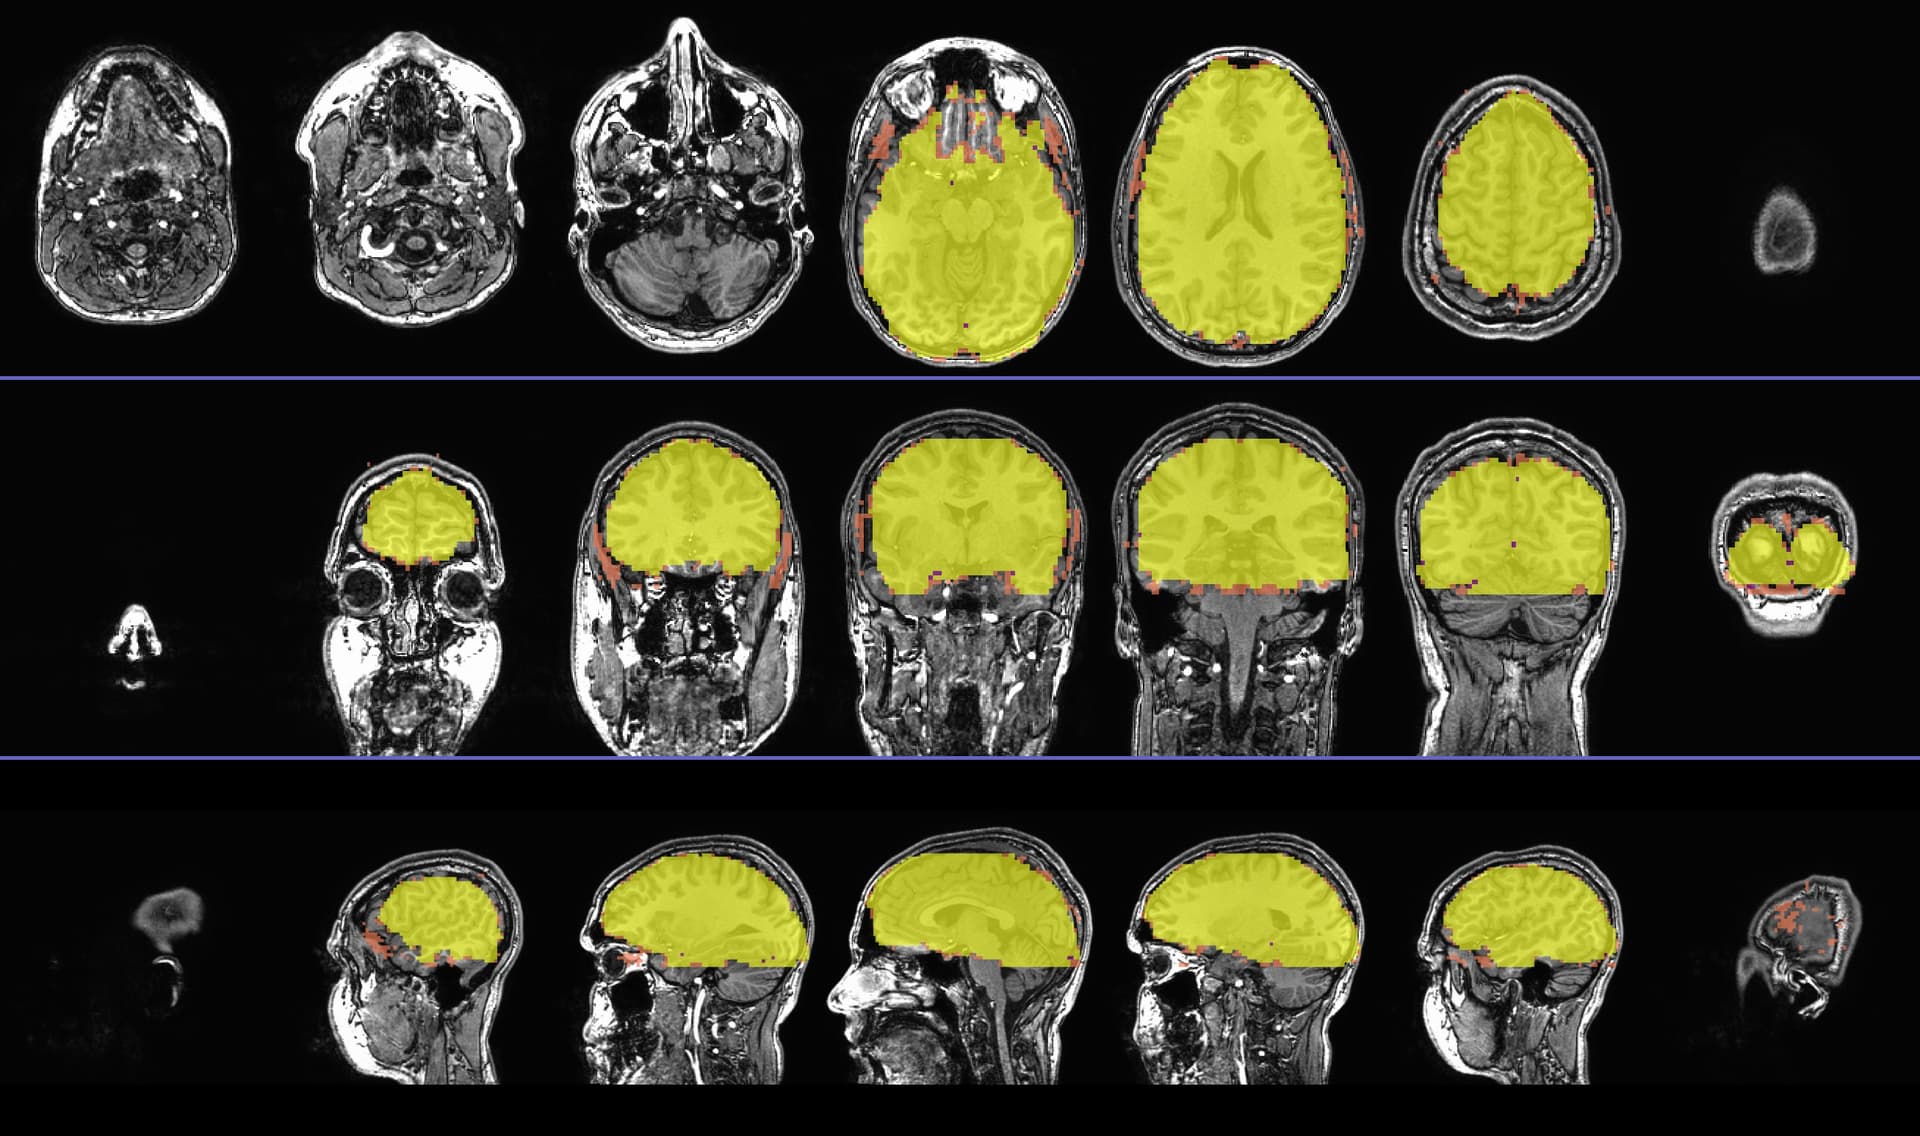

I would love to understand how can I script something to make images like such

I have found some new improvements by ptaylor, but I cannot find a reliable way to produce these images.

So far, code below can produce images like displayed below :